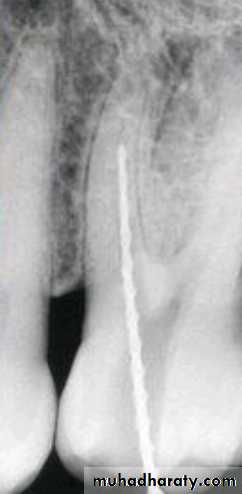

After determining the master apical file, the succeeding larger files are shortened by 0.5 or 1.0 mm increments from the previous file length.

This step-back process creates a flared, tapering preparation while reducing procedural errors.

The step-back preparation is superior to standardized technique in debridement and maintaining the canal shape.

Step-back technique